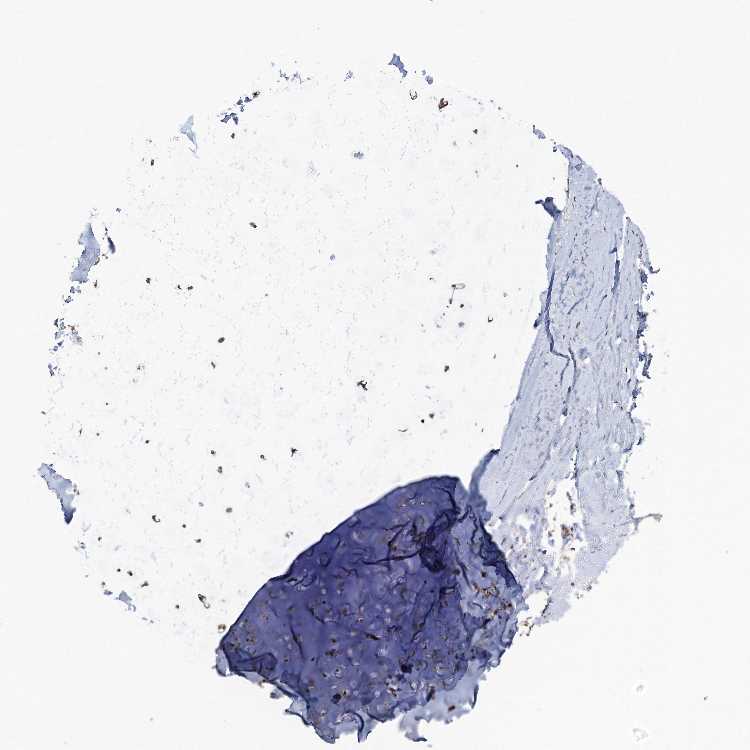

SOFT TISSUE 1 - Antibody stainingi

Antibody staining in the annotated cell types in the current human tissue is reported as not detected, low, medium, or high, based on conventional immunohistochemistry profiling in selected tissues. This score is based on the combination of the staining intensity and fraction of stained cells.

Each image is clickable and will lead to virtual microscopy that enables deeper exploration of all samples and also displays staining intensity scores, fraction scores and subcellular localization as well as patient and tissue information for each sample.

Antibody HPA037773

Fibroblasts Low

Peripheral nerve Medium

SOFT TISSUE 2 - Antibody stainingi

Chondrocytes High

Fibroblasts Medium